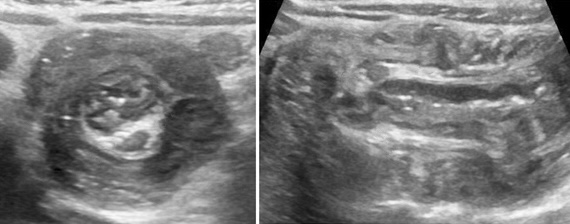

- non compressible, > 6 mm (TDM > 7 mm), hyperhémie, hyperécho autour, 25% stercolithe

- contenu liquidien + ligne hyper (sous-muqueuse) + anneau hypo (musculeuse)

- complications : plastron, abcès, péritonite

arguments pour une invagination iléo-colique

- diamètre > 2 cm et longueur > 3 cm

- ganglion ou appendice dans le boudin

- jonction iléo-colique non visualisée